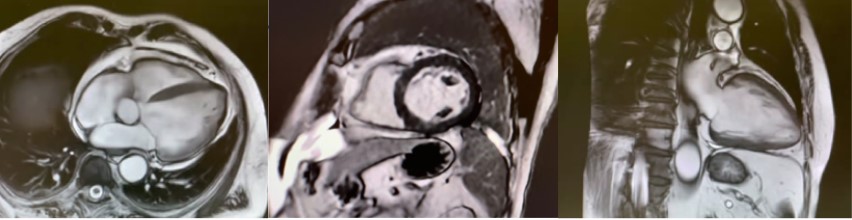

We report the case of a 67-year-old male who presented to a spoke emergency department with marked asthenia and dyspnea following an episode of acute gastroenteritis. Upon triage, the patient was assigned a red code due to hypotension and signs of hypoperfusion. Initial arterial blood gas analysis revealed metabolic acidosis with lactate levels of 2.7 mmol/L. Cardiological evaluation identified new-onset atrial fibrillation and severe left ventricular dysfunction (EF 10-15%) in the absence of ECG alterations suggestive of acute ischemia. Laboratory tests indicated multiorgan failure, with elevated creatinine and troponin levels. Based on these findings, dobutamine infusion was initiated, and the patient was subsequently transferred to a tertiary care center. Within hours, the patient experienced further hemodynamic deterioration, with lactate levels rising to 8 mmol/L, requiring escalation of inotropic support. Low QRS voltage on electrocardiogram compared to a prior tracing raised suspicion of myocarditis, prompting the administration of high-dose methylprednisolone therapy. Despite these measures, the clinical course rapidly progressed necessitating the implantation of IABP and endotracheal intubation. Coronary angiography excluded significant coronary artery disease, while urgent endomyocardial biopsy revealed massive acute necrotizing myocarditis, predominantly lymphocytic. Based on these findings, immunosuppressive therapy with intravenous immunoglobulins was initiated in addition to inotropic support and corticosteroid therapy.Over the following days, the patient demonstrated gradual hemodynamic stabilization, lactate clearance, and partial recovery of ventricular function, preceded by a progressive increase in QRS voltage on ECG. By day 18, the patient exhibited significant improvement, with left ventricular ejection fraction increasing to 30-35% and normalization of most laboratory parameters. Cardiac magnetic resonance imaging revealed minimal late gadolinium enhancement, leading to the decision to delay ICD placement pending reevaluation at 3 months. Therefore, the patient was discharged to a cardiological rehabilitation structure. This case highlights the critical role of early mechanical and pharmacological support, alongside immunomodulatory therapy, in managing fulminant myocarditis. Notably, early electrocardiographic improvement preceded ventricular functional recovery, emphasizing the potential prognostic value of ECG changes.